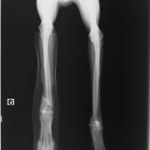

術前レントゲン

術後レントゲン

ペルシャ猫 11ヶ月齢 雄

他院にて左大腿骨遠位の成長板骨折(salter-harrisⅠ型)が認められており、治療相談を目的として来院。当院にて、キルシュナーワイヤーを用いたピンニングにより骨折部位の整復を行いました。術後の経過は良好で、現在も経過観察中です。